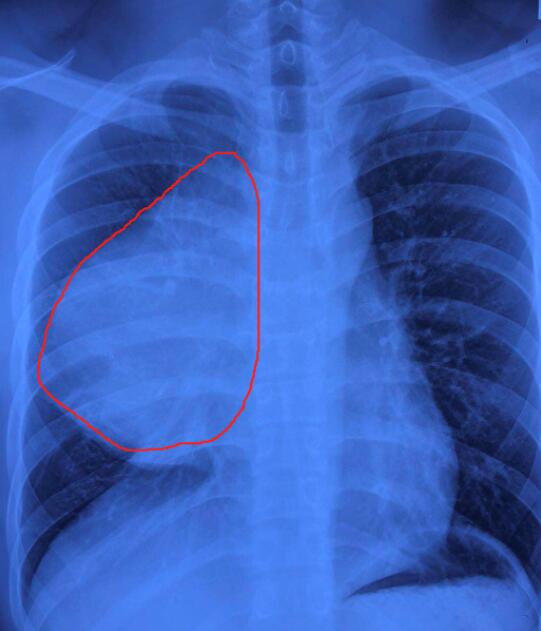

劉先生起初在其他醫院拍片發現,縱隔內巨大佔位病變,於是前往北大深圳醫院就診。北大深圳醫院胸外科主任醫師惠剛介紹,入院後發現,劉先生心肺壓迫癥狀表現嚴重,手部、臉部水腫,呼吸急促,頸靜脈怒張,而且不能平躺。做胸部CT檢查時,發現胸內前縱隔偏右巨大腫物,基本占居了整個右側胸腔,心臟、上腔靜脈、肺組織均明顯受壓。

手術組共同協作,順利完成了前縱隔巨大腫瘤切除術。惠剛介紹,腫瘤術後秤重2.3公斤,就像一個西瓜放在了患者胸腔,壓着心臟、血管,隨時有心臟驟停的危險。順利術後第2天,劉先生手部及臉部水腫明顯消除,能夠平卧睡覺,呼吸平順,心率正常。目前劉先生恢復良好,順利出院。